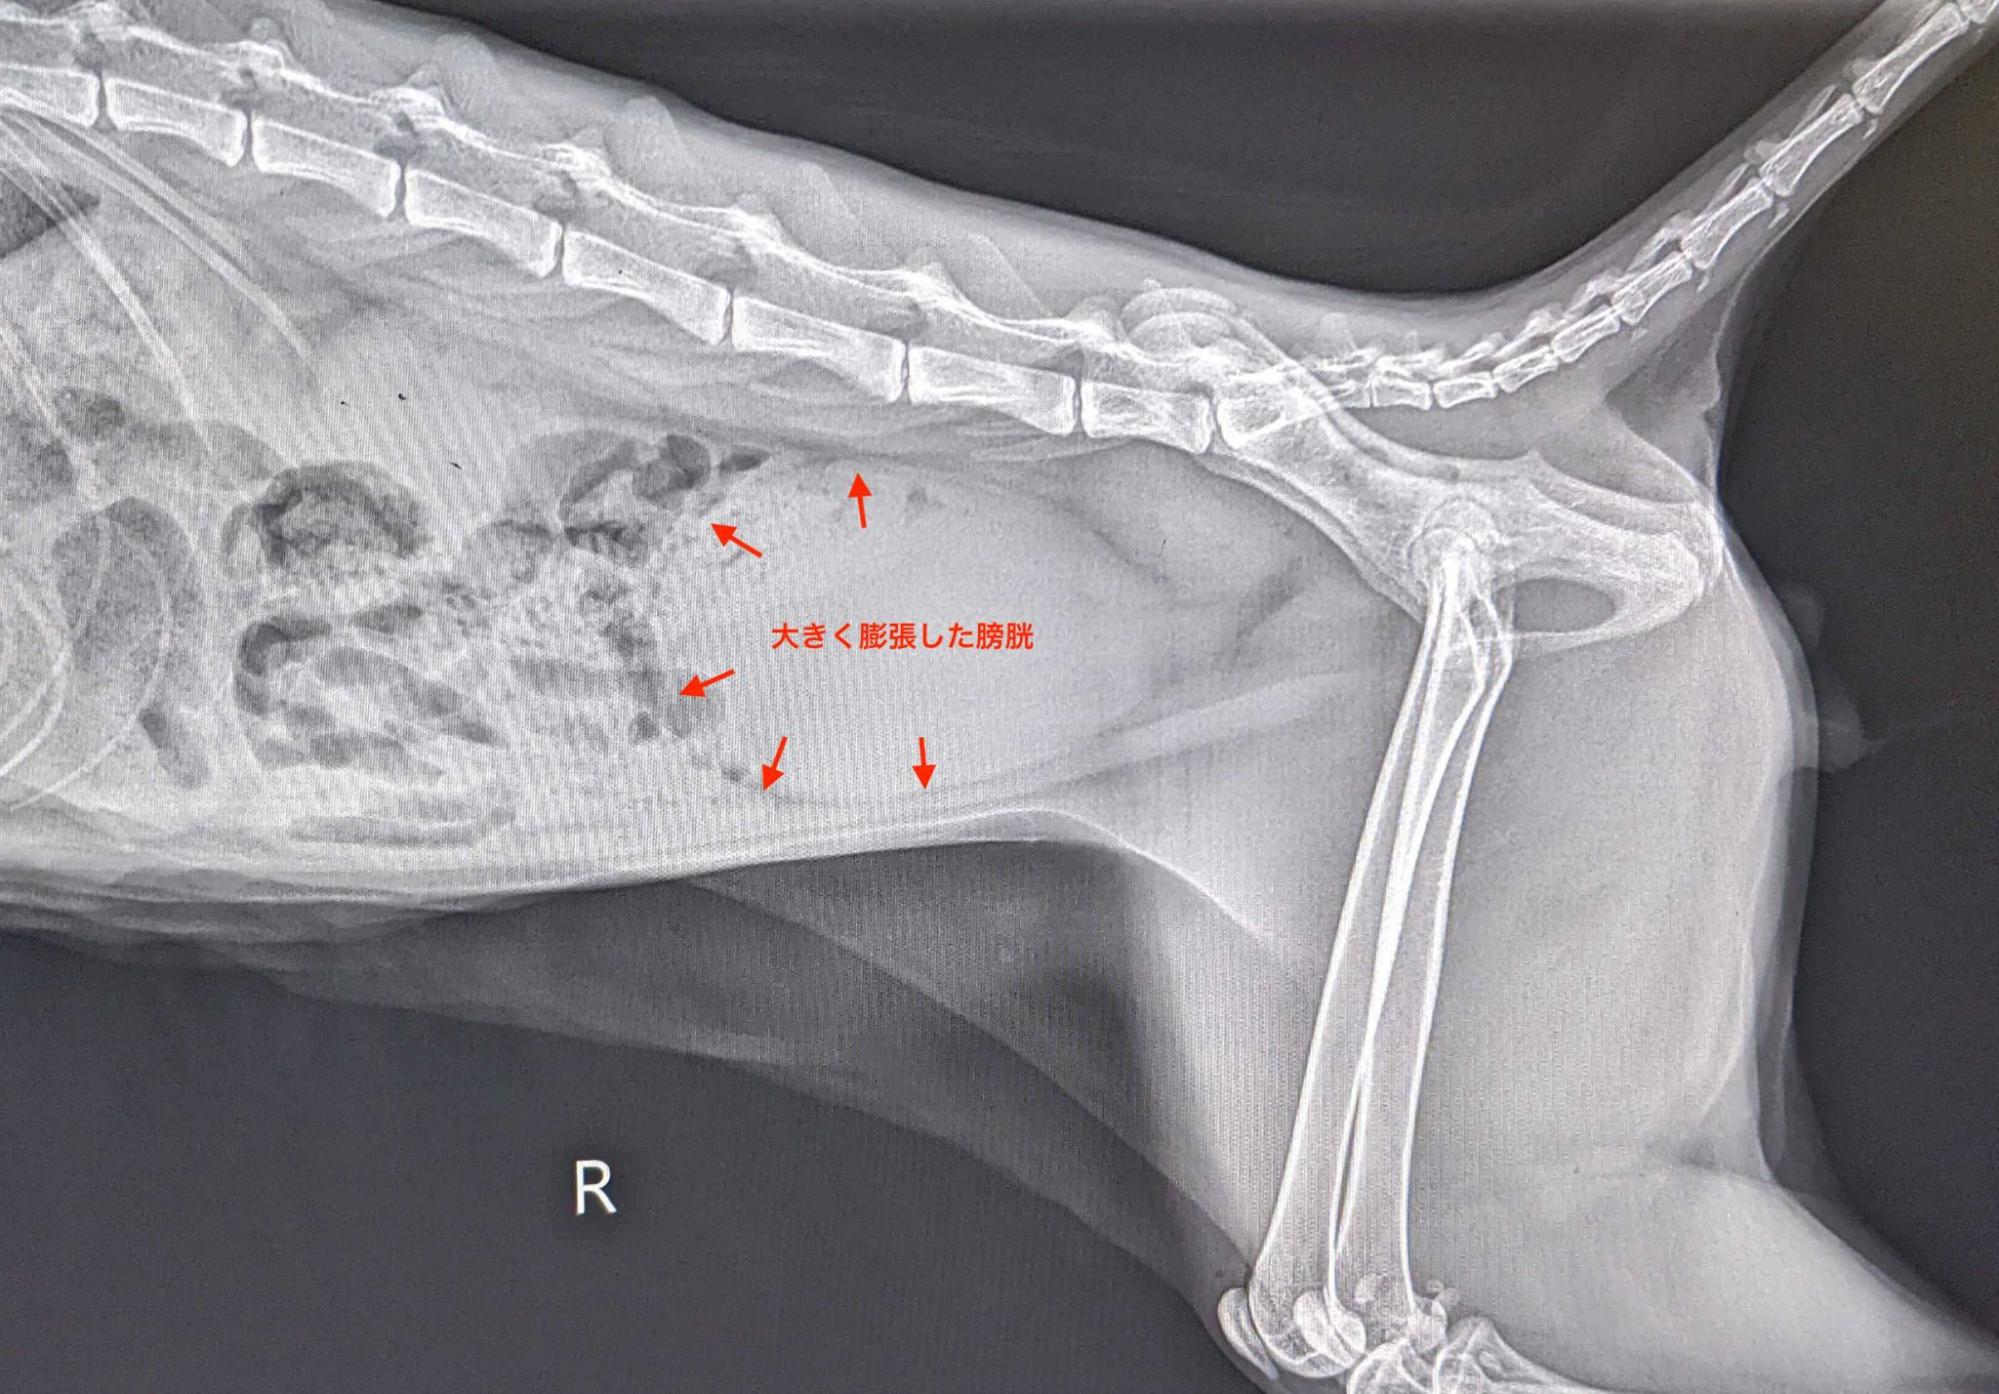

画像:尿道閉塞を起こした猫のレントゲン写真。お腹の半分ほどを膀胱が占めてしまうほどぱんぱんになっている様子がわかります

膀胱炎は、基本的に致死的な状態になることは稀です。しばらく頻尿や血尿や痛みが出るくらいで、亡くなることはありません。しかし、尿道閉塞は違います。膀胱炎や膀胱結石によって二次的に起こる症状の一つで、おしっこが詰まってしまう(つまり、おしっこが出なくなってしまう)状態になります。

尿道閉塞とは、尿の道である尿道が結石などにより詰まってしまい、出したくても尿が出せない状態を言います。主に尿道が狭く曲がりくねっているオス猫に多く見られます。

尿道が詰まってしまうと、本来捨てる必要がある体の老廃物が捨てられなくなります。例えば、カリウムはその代表例ですが、多すぎるカリウムには心臓を止めてしまう作用があります。もちろん、物理的におしっこが溜まりすぎることで、水風船が割れるように膀胱破裂を起こすこともあります。破裂せずとも、腎臓に大きな負担がかかることで急性腎不全を起こすこともあります。こうした結果、死に至ることもあるのです。半日〜1日程度おしっこが出ていない(出したくても出せない)症状が見られた場合は、即病院に連れていってください。